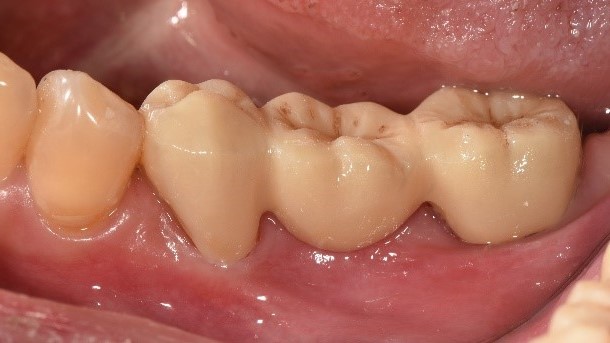

治療中:將牙齒修型、將鐵線拆除

治療後:復原完成,裝上牙橋

治療後X光